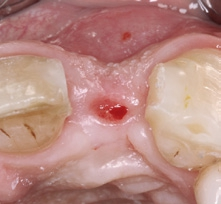

Die Implantatfreilegung mit Weichgewebschirurgie

Nach sechs Monaten Einheilzeit war der labiale Aufbau in einen stabilen Knochen umgebaut und das CERALOG Implantat osseointegriert. Nachdem die Klebebrücke herausgetrennt war, wurde das Implantat mittels modifizierter Rolllappentechnik freigelegt. Der Anteil der krestalen Gingiva über dem Implantat wurde mit einem diamantierten Schleifkörper deepithelisiert (Abb. 15). Mit einem wellenförmigen parakrestalen Schnitt wurde der Zugang zur Implantatverschlusskappe geschaffen, indem das nach labial gestielte Weichgewebe über dem Implantat mobilisiert und angehoben wurde. Anschließend wurde die flache Kappe entfernt und ein 4 mm hoher Gingivaformer eingeschraubt. In das labiale Weichgewebe wurde eine Tasche über dem Periost präpariert, in die das umgeklappte Bindegewebe eingeschoben wurde (Abb. 16–19). Mit einem 6.0 Prolene-Nahtmaterial wurde das Weichgewebe dicht um den Gingivaformer vernäht (Abb. 20). Die von basal gekürzte temporäre Klebebrücke befestigten wir adhäsiv an den Nachbarzähnen.